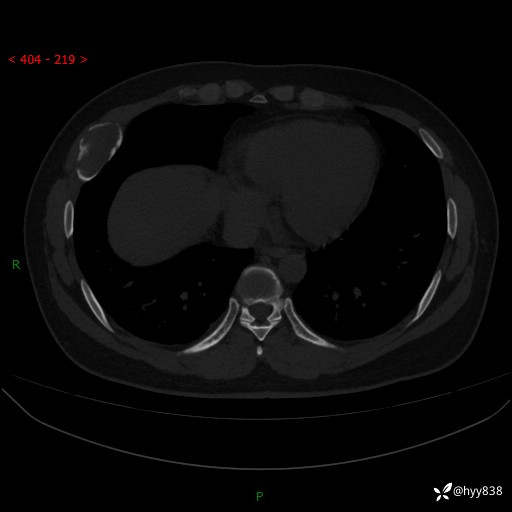

年轻小伙,右侧胸部疼痛4天余。病理科说肯定不是骨纤,那是啥---结果公布~

年龄:24岁

主诉:右侧胸部疼痛4天余。

现病史:患者约4天前突发右侧胸部疼痛,无瘙痒,无头痛、头晕,无心慌、胸闷、呼吸困难、咳嗽、咳痰、咯血,无腹痛、腹胀等不适,未作进一步诊治。于2024年5月外院行胸部CT平扫示右侧肋骨骨质改变。现为求进一步治疗,遂于我院就诊。门诊以“胸壁肿物”收入我科。 患者自起病以来,精神可,睡眠可,饮食可,大小便正常,体重无明显改变。

胸部CT平扫